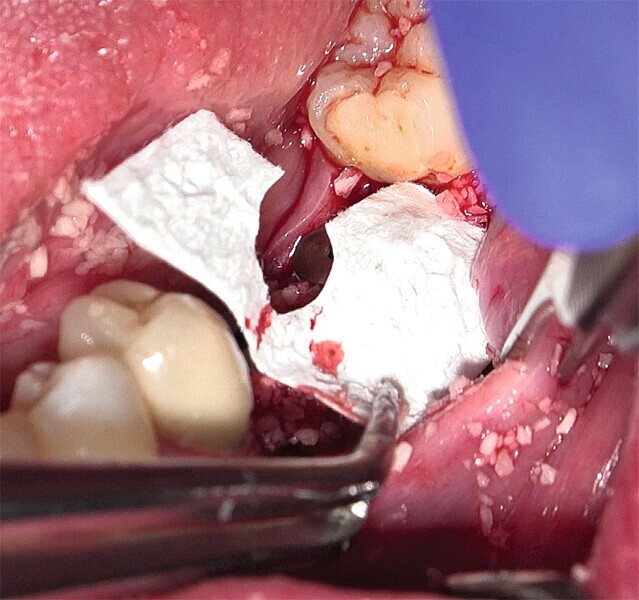

Fig. 29 : Augmentation osseuse latérale (régénération osseuse guidée) au moyen d’une allogreffe constituée d’un substitut osseux, simultanément à la pose des implants.

Fig. 30 : Augmentation osseuse latérale (régénération osseuse guidée) au moyen d’une allogreffe constituée d’un substitut osseux, simultanément à la pose des implants.

Fig. 31 : Mise en place d’une membrane de collagène à titre de barrière de protection et suture.

Fig. 32 : Mise en place d’une membrane de collagène à titre de barrière de protection et suture.

Fig. 33 : Mise en place d’une membrane de collagène à titre de barrière de protection et suture.

La crête alvéolaire au niveau du site de la molaire inférieure était trop étroite pour permettre la pose prédictible d’un implant sans une augmentation osseuse préalable. Des implants deux pièces en zircone ont été mis en place, simultanément à une augmentation osseuse latérale, au moyen d’une allogreffe et d’une membrane de collagène résorbable (Figs. 25–34).